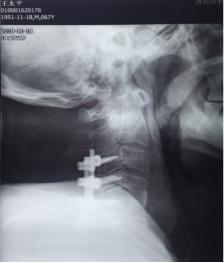

术 前

11月13日行手术治疗,后前路联合手术。先行颈后路切开,颈3-6椎体侧块螺钉固定,再行前路颈4.5间盘以及颈前脓液清理,椎间隙植骨融合术。术中见颈4.5椎间隙前缘被一直径1.5㎝肿物包裹,打开后,可见其内少许米汤样脓性液,肿块壁为脓性物。间盘内充填相同物,上、下缘软骨板漂浮,翘起,上下椎体相邻面骨质酥脆,同时后缘有大量不良增生物,骨钩分离后,可见自颈5椎体后缘,流出同样的米汤样脓液。彻底清理脓性液,充分刮除椎体不良骨质。大量生理盐水冲洗,取三面皮质髂骨块置于椎间隙,敲紧。术后前侧放引流管于脓腔间隙。术后留置3.5天。术中留取的脓液细菌培养仍为阴性,刮出的椎间盘及囊壁病检结果显示为化脓性炎表现。术后继续抗生素治疗,患者体温正常,四肢肌力改善明显,下肢肌力术后第2天恢复至2级。上肢肌力4级弱。躯干部位感觉平面下降至乳头以远,大小便功能改善不明显。